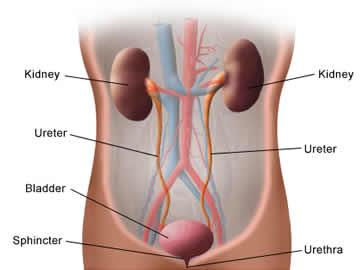

Kidney stone

For those who suffer from recurrent kidney stones, homeopathic treatment can be very effective and a safe alternative to any kind of surgical intervention. Homeopathic ... Full story

Kidney stone

Make a powdered preparation of equal quantities of the bark of three-leaved caper tree (varun), puncture pine (gokhru), thatch grass (kas) and horse gram (kulthi). ... Full story